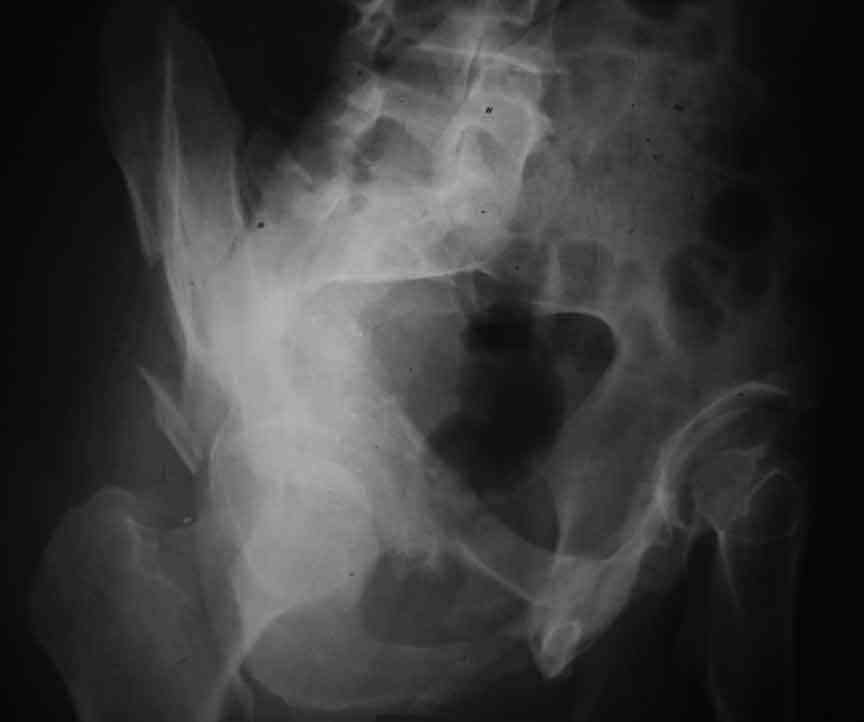

From the x rays it appears like a bicolumnar fracture with iliac extension (AO C1).

CT scan is mandatory to evaluate such fractures more accurately and also to plan the treatment and surgery Most of the bicolumnar fractures of the high variety in experienced hands can be managed thro the ilioinguinal approach

I am sending another iliac view, and a marked version of the AP I already sent. In this AP, the

proximal part of the greater sciatic notch as well as the distal parts of the ilioischial and iliopubic lines are marked with a grey interrupted line. A white interrupted line marks what could be an exit through the obturator foramen, or so I assume.